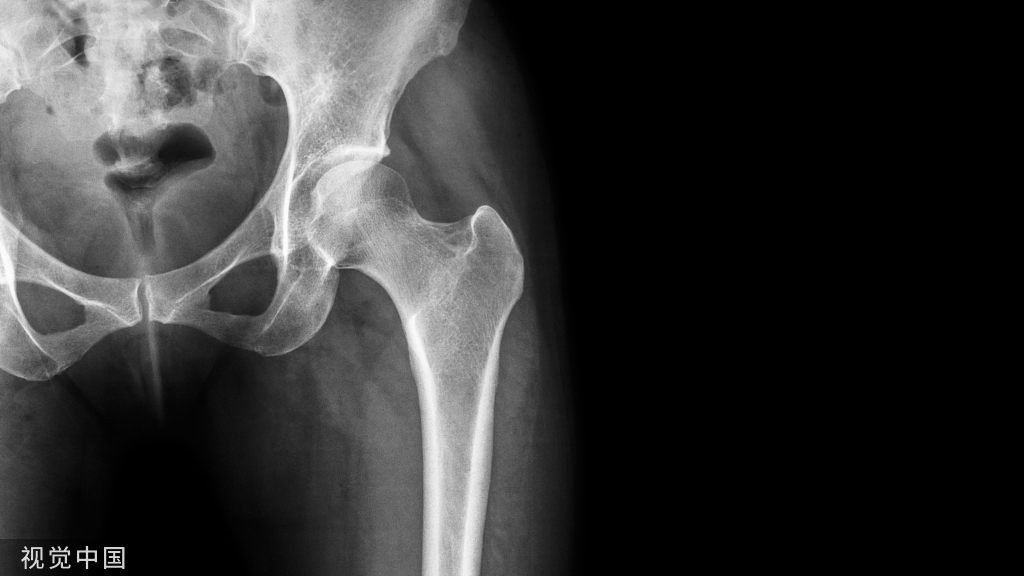

(1)骶岬在S1椎弓根块的前方,而骶骨翼是骶骨岬与骶髂关节前面之间的凹陷,走向骶岬的螺钉容易损伤前方结构;髂骨增厚处和S1椎体是骶髂螺钉固定点。

(2)S1骶孔的一半以上由S1椎体形成,S1神经根管从S1 骶孔的下、前和外侧穿过,如果螺钉位于S1椎体的下半部,则必须指向S1神经根管的前方,偏后则会损伤S1神经根。

(3)S1节段周围的结构有:S1神经根管和S1骶孔在S1椎弓根块的下缘,S1椎体后方是马尾神经,骶骨翼前方是髂内血管、L5神经根 、输尿管;膀胱在S1椎体的前方,S1椎体的上方是椎间盘,以上重要结构都不能损伤。

(4)骶髂螺钉必须沿着S1椎弓根块进入椎体,保持全程在骨内。第一枚螺钉在上方,正位透视位于椎体中部靠近上终板,第二枚螺钉位于椎体前半部的下方。( 参考文献:Marvin Tile主编,邱贵兴主译,骨盆与髋臼骨折,2006)